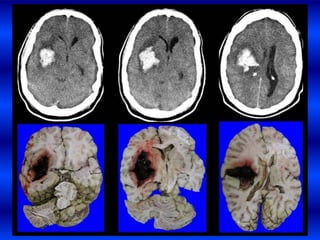

EXPANSIÓN TEMPRANA

DE HIC.

Pte masculino, raza negra,

APP de HTA que sufre una

HIP subcortical derecha

que en los primeros

80mtos presenta cefalea,

disartria ligera y

hemiparesía izquierda en

la segunda TAC hay un

deterioro progresivo de la

conciencia , midriasis

derecha por hernia uncal y

apertura a ventrículos

laterales.

• 34.

EXPANSIÓN TEMPRANA DE HIC. Ptemasculino, raza negra, APP de HTA que sufre una HIP subcortical derecha que en los primeros 80mtos presenta cefalea, disartria ligera y hemiparesía izquierda en la segunda TAC hay un deterioro progresivo de la conciencia , midriasis derecha por hernia uncal y apertura a ventrículos laterales.